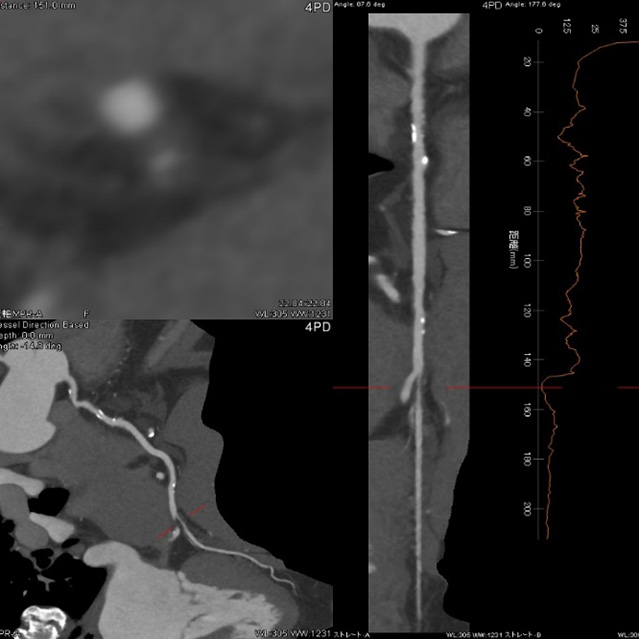

画像診断装置・放射線治療装置紹介

X線CT装置

64列 MDCT Aquilion CX (canon)

80列 MDCT Aquilion PRIME (canon)

80列 MDCT Aquilion PRIME SP(canon)

大きなトンネルの中に体を入れて、X線をあてて体の輪切りの写真を撮ります。CT検査には、単純CT検査と、造影剤を注射して撮影する造影CT検査があります。